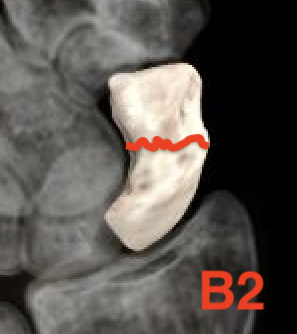

Type B: Unstable fractures

- B2: complete waist

| B1: Distal oblique | B2: Complete waist | B3: Proximal pole | B5: Comminuted |